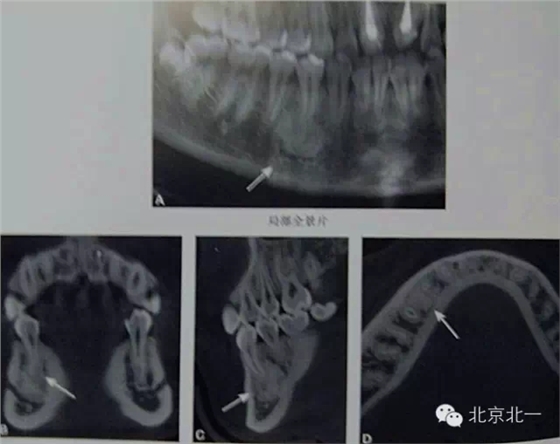

右下頜C4根尖區(qū)課件一類圓形高密度影,與周圍骨質(zhì)分界清晰,C4牙周膜影像連續(xù)、完整,下頜骨未見膨隆。

【CBCT表現(xiàn)】:

在CBCT上,根尖型骨島無低密度帶狀影包繞,與周圍骨質(zhì)分界清晰,具有特征性的毛刷樣邊緣,且其發(fā)生區(qū)域的牙根牙周膜影像連續(xù)、完整、不導(dǎo)致頜骨的膨隆。